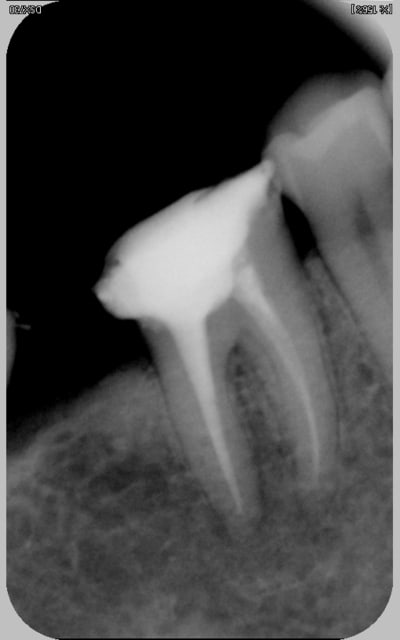

pffff...vi bin deux secondes ! :):) quand ce sera fini ça n'aura pas grand intéret , juste j'ancrerai pour repartir les contraintes différemment)

bien sur le canal est repris, mais juste parce que j'ai dû y retourner pour déposer ce maudit truc si bien collé,et je ne vais pas dans les canaux mesiaux

largement? tenon passif noyé dans matrice collée, un plaisir c'est sur:)

sorry, fallait trouver la rd (heu...cherche pas suis au bout:):) )

merci mon nadhoc! mais c'était pas de la feraille , c'est cette nouvelle mode du tenon plastoc non ajusté au canal (ou plus exactement sous ajusté) et noyé dans une résine collée aux parois (je crois qu'il y a eu un article récemment dans l'ID)

le but étant de réduire, ou plûtot de répartir astucieusement les contraintes en caressant les coef d'élasticité dentine, resine, pivot etc...parce qu'on veut éviter qu'un pivot metal, ajusté au canal, n'amorce felures et fractures

alors on voudriat coller (tiens! un bouble-sens!) aux résistances naturelles de la structure dentaire.

Moralité, comme naturellement les contraintes s'accumulent au tiers cervical, bin c'est là que ça a cassé...c'était du trop good job! :)

l'est pas bonne ma rd? technique des plans parralleles sans correction pourtant, pis meme avec mon doigt, par dévouement au soin:)

Curieux, mon athos, les tenons carbonne sont moins opaques aux RX, d'habitude! ; cela dit, je trouve ta radio tres bien, peut etre qu'en étant puriste, il faut adapter en rendant paralleles l'axe de la dent et l'axe principal -ici vertical-, mais ne chipotons pas, je serais incapable de faire mieux, sauf coup de chance!)

pour être sincère adhoc, a la premiere radio l'opacité du tenon m'a si peu marqué que je ne l'avais pas vu:)